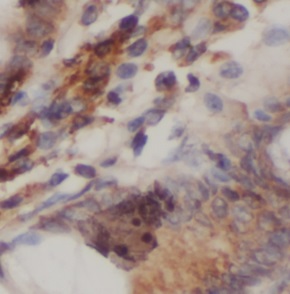

| 验证图片 | Immunohistochemistry of paraffin-embedded human colon cancer using FNab10092(PRKCQ antibody) at dilution of 1:50 |